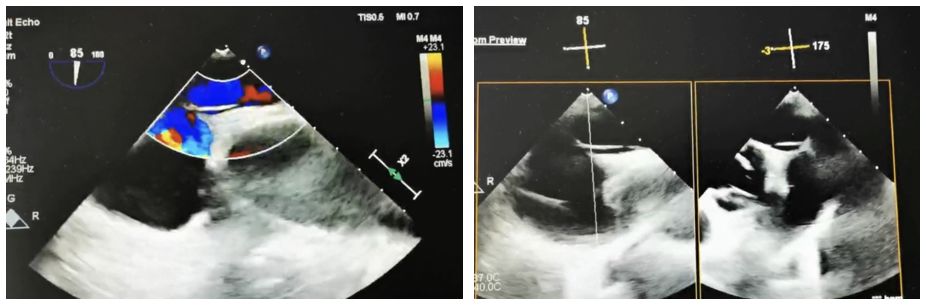

Case Information: A 60-year-old male patient was admitted to the neurology department after experiencing "left-sided limb weakness". The patient underwent a routine transesophageal echocardiogram (TEE), which revealed a patent foramen ovale (PFO) (congenital type, 2.4mm in width, 33mm in length, with moderate shunting). Right heart echocardiography and bubble tests confirmed a grade II shunt.

Strategia kliniczna: Wybraliśmy BDPFO-I 2828 symetryczny okluder, aby zapewnić optymalne zamknięcie. W fazie uwalniania do pozycjonowania używano obrazowania DSA, podczas gdy naprowadzanie ultrasonograficzne było stosowane głównie w celu zapewnienia dokładnego rozmieszczenia.

Podsumowanie przypadku: Ze względu na długość tunelu konwencjonalne prowadniki cewnika i podparcie osłony przegrody nie były skuteczne. W szczególności zastosowano w tym przypadku prowadnicę wieńcową połączoną z osłonką punktową przegrody, która z powodzeniem przekroczyła przegrodę. W przypadku stosowania tradycyjnych metalowych oklustrów do długich tunelowych zamknięć PFO, sztywny materiał i stała pozycja w talii często uniemożliwiają pełne rozszerzenie lewego dysku. Może to spowodować wciągnięcie dysku do tunelu, prowadząc do szczątkowego manewrowania. Natomiast biodegradowalny okluder, dzięki swojej silnej podatności, pozwolił talii na pełne wypełnienie tunelu i uzyskanie skutecznego zamknięcia.